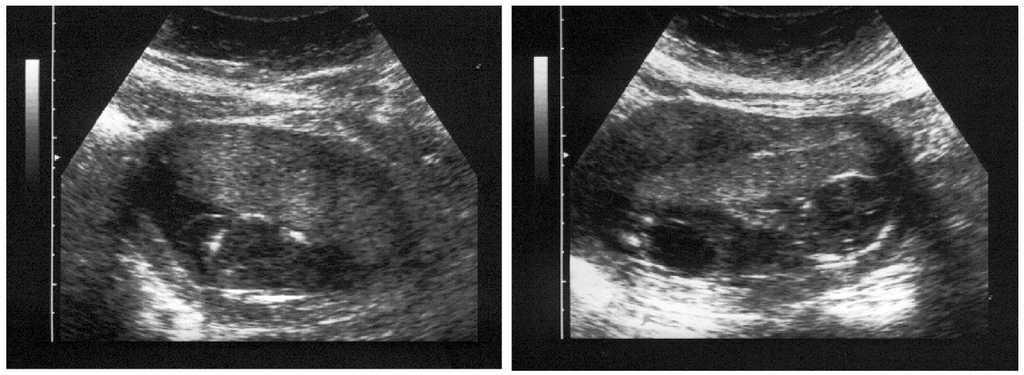

Paciente de 31 años, que acude a la Unidad de Ecografía y Medicina Fetal del Hospital Universitario de Canarias para una evaluación gestacional rutinaria en la semana 16 cronológica gestacional. En la ecografía se detecta una gestación que biométricamente corresponde a 15 semanas, con un feto que muestra datos dismorfológicos consistentes en megavejiga urinaria con hipertrofia de paredes vesicales e hidronefrosis más visible en el riñón derecho, así como higroma quístico del cuello de 46 mm de sección (fig. 1). Dada la evidente relación del cuadro con una cromosomopatía, se practica amniocentesis.

Figura 1.Hallazgos ecográficos destacados (16 semanas). A) Higroma quístico. B) Megavejiga.